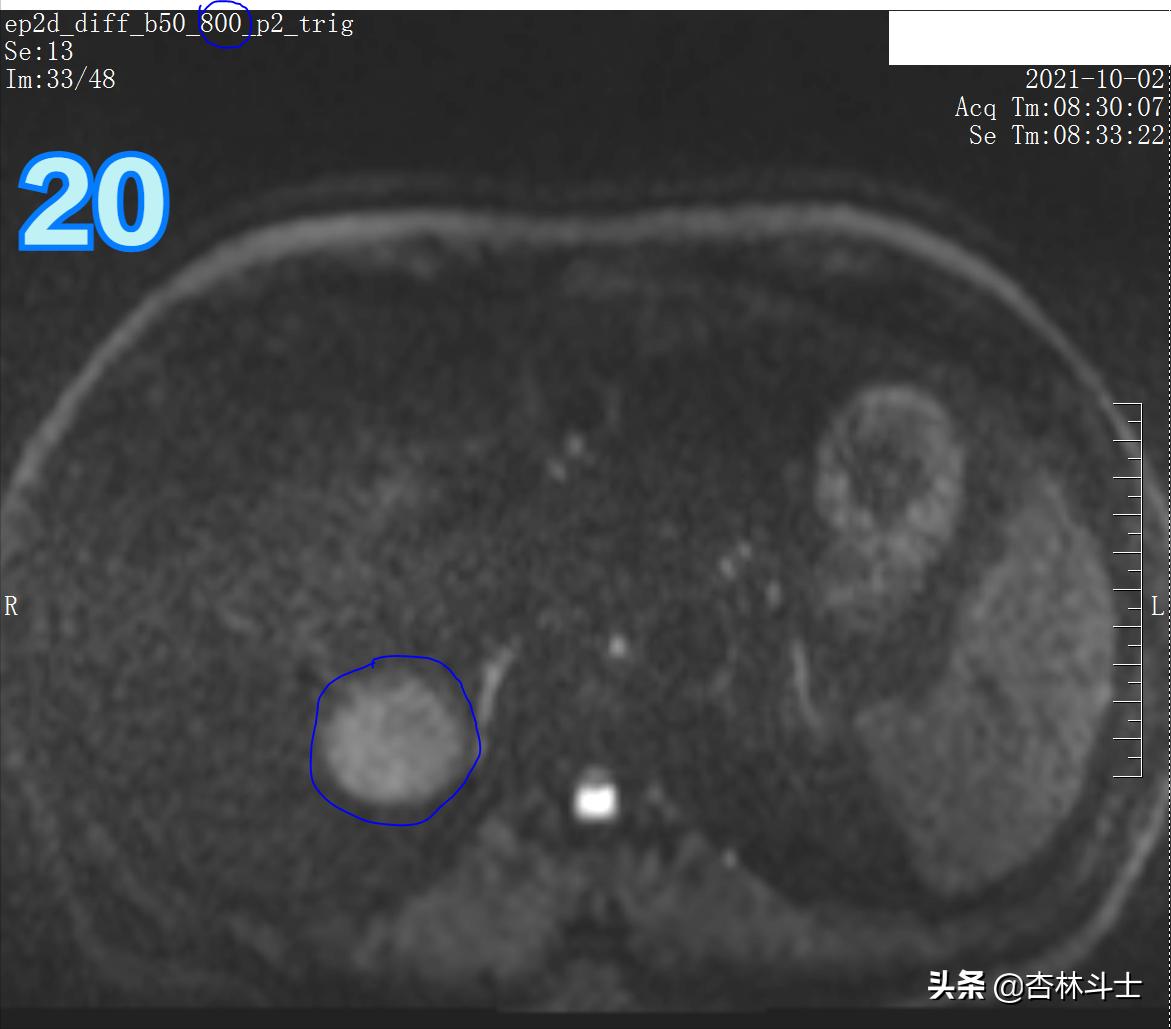

DWI

图19、20 病灶弥散明显受限。